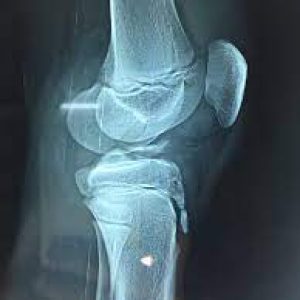

- Preoperative Assessment: Comprehensive evaluation, including physical examination, imaging studies (X-rays, MRI), and assessment of knee stability and function.

- Fixation Technique: Specialized fixation devices, such as screws, anchors, or sutures, are used to secure the ACL fragment back to its anatomical insertion site.